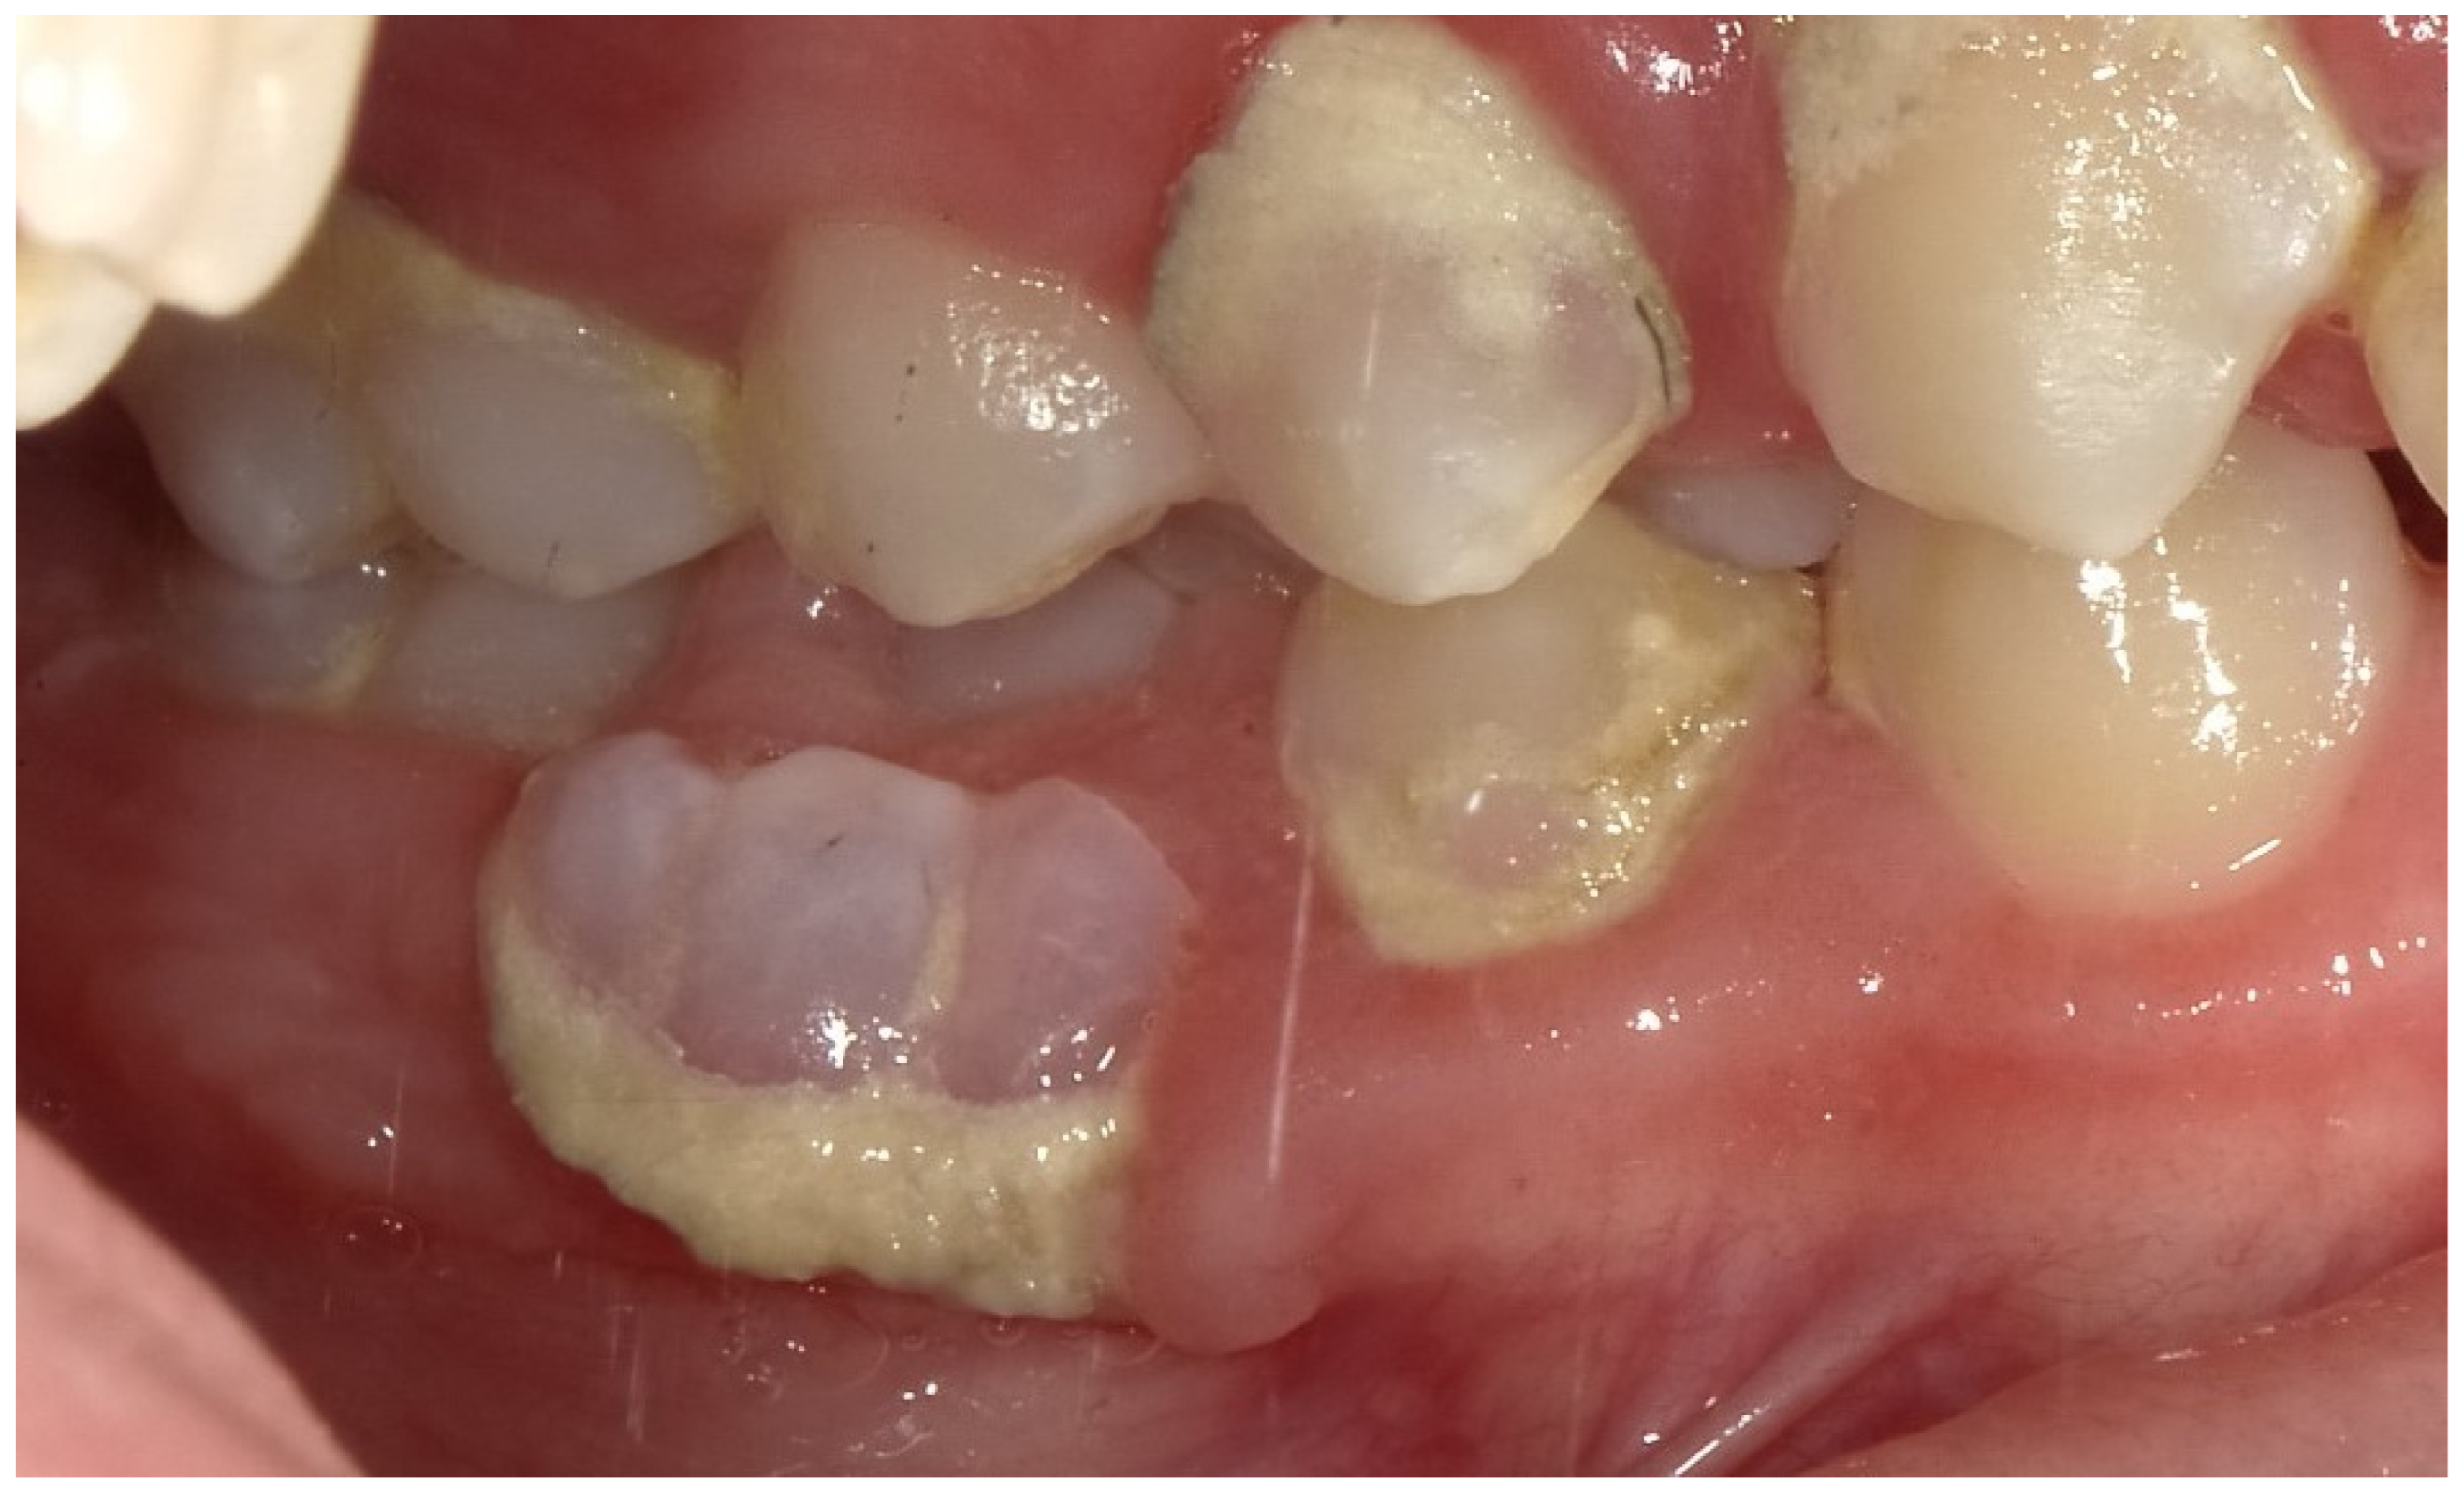

2.2. Clinical Findings

2.3. Diagnostic Assessment